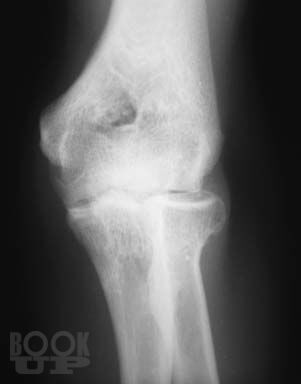

Книга посвящена сложному и разнообразному разделу травматологии – диагностике травматических повреждений крупных суставов у взрослых и детей. Приведены основные рентгеноанатомические сведения о суставах. Дана рентгенологическая характеристика разнообразных повреждений костей и мягких тканей, доступных рентгеновскому исследованию. Представлена рентгенологическая картина посттравматических, в том числе послеоперационных воспалительных осложнений – артритов.